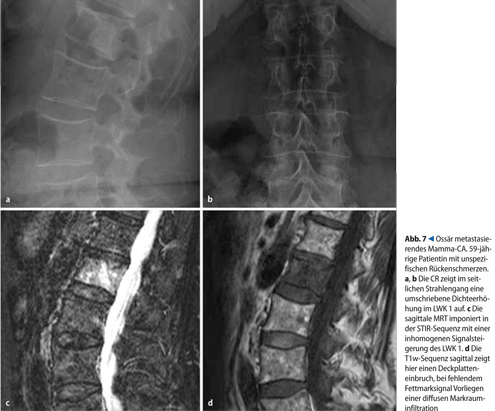

Sie besitzt die höchste Sensitivität zum Nachweis tumoröser und entzündlicher Prozesse und wird zur Klärung von Ausbreitung und Beziehung fraglicher Raumforderungen zu den intraspinalen Strukturen eingesetzt als auch zum Staging und zu Verlaufskontrollen primärer Wirbelsäulentumoren. Eine Zuordnung der intraspinalen Raumforderung zu einem der drei Kompartimente extradural, intradural-extramedullär oder intradural-intramedullärwird in der Regel erst durch die MRT ermöglicht (s.Tab. 4,. Abb. 7, 8).